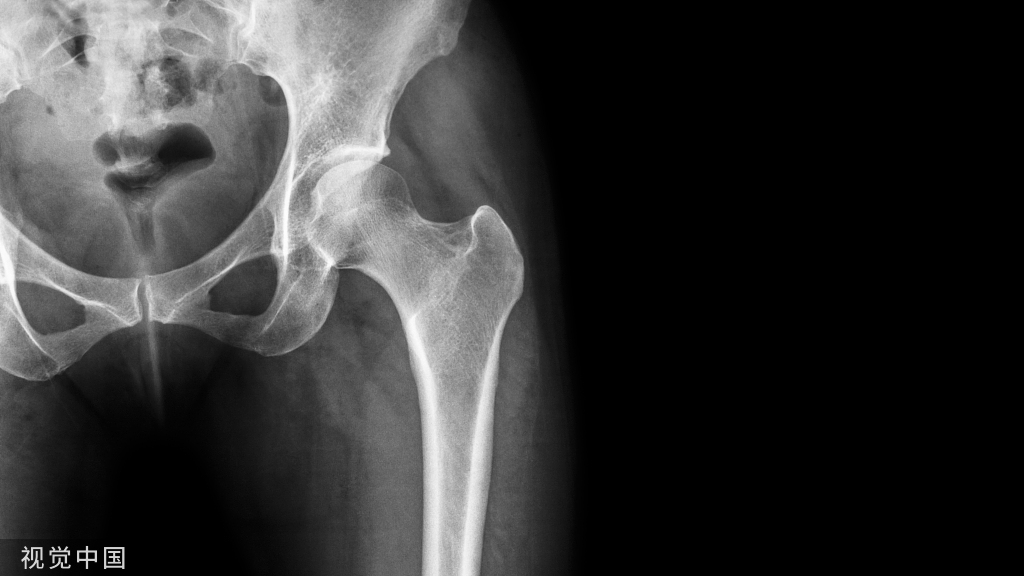

术中C臂头尾侧倾斜20°-30°,左右斜45°透视,确保钉道在泪滴内。注意示意图中球管的位置,不要摆反了。辐射量也小一些 骨科手术C臂透视防护指南

正位片透视钉道在坐骨切迹上方。